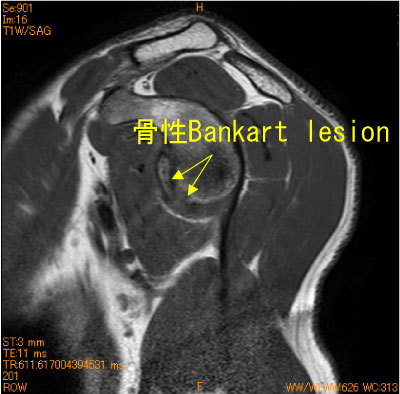

亜脱臼後変化(骨性Bankart lesion)-肩関節MRI-

骨性Bankart lesion、新鮮なHill-Sachs lesionを認めている。

![]() Obl. Sag T1WI |